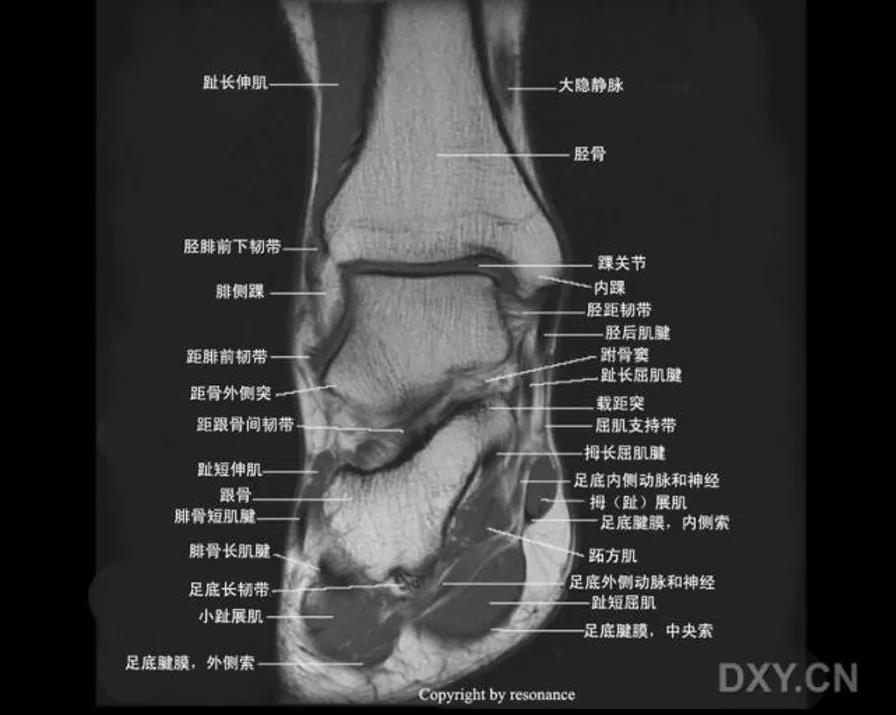

MRI: